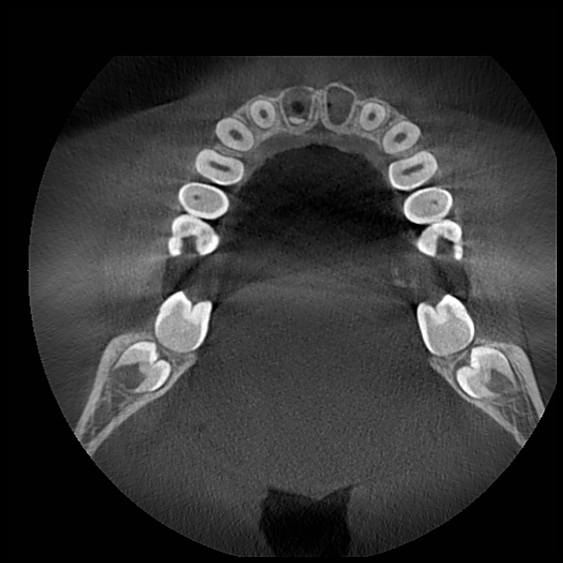

Компьютерная томография зуба позволяет получить всесторонний снимок для сбора полных данных о его состоянии. 3Д снимок челюсти позволяет оценить состояние еще не прорезавшихся зубов, корневых каналов, внутренних повреждений. Его используют при терапевтическом, ортодонтическом, ортопедическом, хирургическом лечении и в детской стоматологии.

3Д рентген зуба гораздо лучше обычного снимка. Каждый зубной ряд имеет массу анатомических особенностей, которые необходимо учитывать при лечении. Их нельзя увидеть невооруженным взглядом и даже на рентген они попадают не полностью, но КТ высветляет все подробности.

В отличие от рентгена, где изображение получается плоским, 3Д-модель врач может повернуть под любым углом, чтобы увидеть все детали. А главное, здесь отсутствуют искажения и помехи, которые могут повлиять на результат лечения.